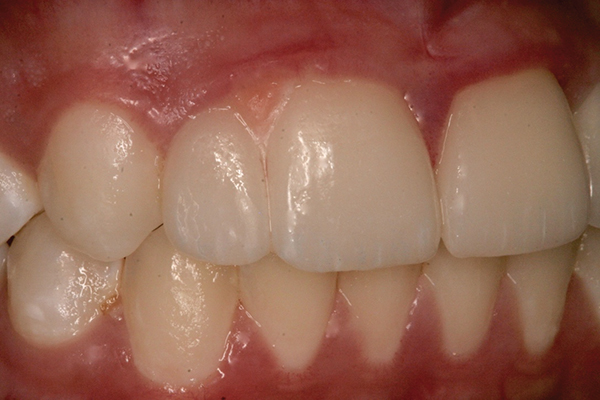

Fig 4 and Fig 5. The fused tooth was carved to resemble two teeth, matching the width of the created tooth central to tooth No. 9.

Using the wax-up as a guide, a composite restoration was fabricated for fused teeth Nos. 7 and 8 by roughening the affected area without pulpal exposure, etching the enamel, and applying primer and adhesive. Composite shade A1 was bonded to the mesial and distal surfaces, with gingival dark composite applied to the cervical “interproximal” region. The tooth was then carved to resemble two teeth, matching the width of the created tooth central to tooth No. 9 (Figure 4 and Figure 5). The patient and her family were very pleased with the result, and no postoperative sensitivity was reported.